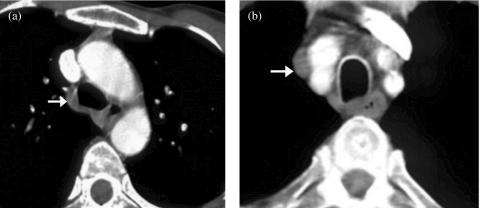

Effective treatment for carcinoma of the lung remains one of the biggest challenges in oncology. Radical radiotherapy may be a curative option for patients who are unsuitable for radical surgery either because of disease stage or because of co-morbidity. Long-term disease control with radical radiotherapy is disappointing with only about 6% of patients treated being alive at 5 years. Technological advances involved in the planning and delivery of radiotherapy may improve this. The advent of conformal radiotherapy, utilizing computed tomography and three-dimensional planning systems, allows much more accurate shaping of the radiation fields. This greater accuracy of target volume definition facilitates a reduction in the radiation dose to normal tissues, allowing for dose escalation to the tumour. Delineation of the target volume can be problematic. Conventional CT has limitations in term of distinguishing between benign and malignant tissues, e.g. the size criteria for involved lymph nodes. The oncologist uses a combination of radiological and clinical information when defining the target volume but their radiological interpretation of imaging is inferior to that of a radiologist. The Royal College of Radiologists (RCR) issued guidance in 2004 on the optimal imaging strategies for common cancers. These guidelines address issues regarding the localisation and staging of cancers and treatment planning, and also reporting and training. They recommend the development of closer links between radiologists and oncologists to optimise the interpretation of imaging and target volume definition. This article aims to briefly explain the planning process involved in irradiating lung cancers, highlight problematic areas and suggest ways in which co-operation with radiologists may improve the delivery of radiotherapy and therefore the treatment outcomes for this group of patients.

肺癌的有效治疗仍然是肿瘤学领域最大的挑战之一。对于因疾病分期或合并症而不适于根治性手术的患者,根治性放疗可能是一种治愈性选择。根治性放疗的长期疾病控制效果令人失望,接受治疗的患者中只有约6%能存活5年。放疗计划和实施过程中的技术进步可能会改善这一情况。适形放疗的出现,利用计算机断层扫描和三维计划系统,能够更精确地塑造辐射野。靶区定义的更高准确性有助于减少对正常组织的辐射剂量,从而可以提高肿瘤的照射剂量。靶区的勾画可能存在问题。传统CT在区分良性和恶性组织方面存在局限性,例如受累淋巴结的大小标准。肿瘤学家在定义靶区时会综合运用放射学和临床信息,但他们对影像的放射学解读不如放射科医生。英国皇家放射科医师学院(RCR)在2004年发布了关于常见癌症最佳影像策略的指南。这些指南涉及癌症的定位、分期和治疗计划等问题,以及报告和培训。它们建议放射科医生和肿瘤学家建立更紧密的联系,以优化影像解读和靶区定义。本文旨在简要解释肺癌放疗的计划过程,突出存在问题的领域,并提出与放射科医生合作可能改善放疗实施从而提高这类患者治疗效果的方法。